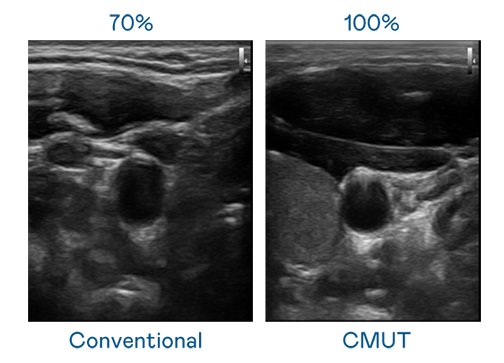

CMUT 技術是一種用電容式微機電元件來產生超音波訊號的技術。與傳統 PZT 壓電式技術相比,CMUT 頻寬增加 30%,更寬頻的超音波訊號讓影像解析度大幅提升,是實現高影像品質醫療超音波掃描、促進精準醫療發展的關鍵技術。

大頻寬帶來超清晰影像

超音波影像的解析度高低,首先取決於探頭能發出的訊號頻寬。新官人我耍迅雷下载mp4 CMUT 可提供高清晰的超音波訊號,提供高頻寬、高靈敏度、影像紋理細節更高的超音波影像,協助醫護人員縮短影像判讀時間及利用精準的醫療影像進行診斷。